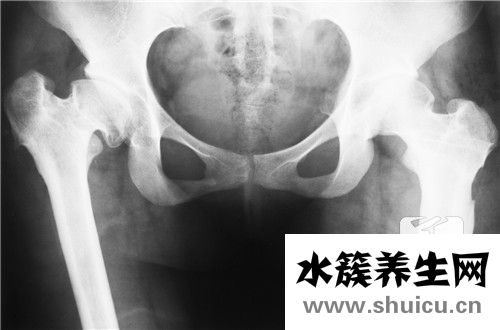

骨盆是我們人體的關鍵部位。有些人經常感到骨盆疼痛,尤其是當他們站起來或坐下時。這種情況主要是由于骨盆肌肉勞損或者過度運動導致的乳酸菌過多。這種乳酸菌還沒有被消耗掉,人體已經造成了過度積...